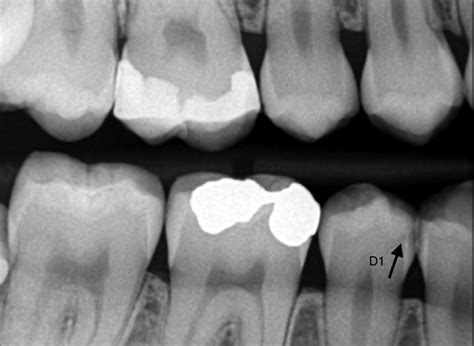

La cuestión es, ¿cómo saber qué estamos delante de una caries? En el resultado, las caries suelen verse como áreas más oscuras del diente, debido a la menor densidad del tejido afectado por la desmineralización.

Estudio radiológico de la caries.

- Caries interproximales: Una caries interproximal se forma entre los dientes y es, probablemente, el tipo de caries más difícil de detectar sin una radiografía.

La segunda es que la dirección de los rayos no es la ideal para extraer información de las áreas de contacto, principal zona de producción de las caries susceptibles de diagnosticarse radiológicamente. En las primeras fases de su desarrollo, la caries que afecta al esmalte aparece como una sombra, normalmente situada inmediatamente por gingival del área de contacto. La morfología de la imagen es triangular, con vértice dirigido a la dentina y base exterior.

Está demostrado que existe un decantaje entre la afectación radiográfica y la real, de forma que la imagen radiológica está retrasada respecto a la situación histológica. El esmalte puede estar, cuantitativamente, afectado de dos formas distintas: La mitad externa o todo su espesor.

Dicha afectación radiológica no está de acuerdo con la afectación clínica: En un estudio clínico realizado por algunos autores, se encontró afectación dentinaria histológica, diagnosticada mediante colorantes, en un 51’43% de los casos en los que la lesión radiológica estaba confinada al esmalte. Es decir, si el esmalte está afectado en algún grado, más de la mitad de los casos ya sufren de afectación dentinaria.

Cuando la imagen radiológica es de afectación dentinaria, ésta es en forma de una radiolucidez globulosa, generalmente mal definida y en relación casi siempre con una caries de esmalte. La disposición general de dicha imagen es invertida respecto a la del esmalte: Triangulo de base exterior y vértice en dirección pulpar.